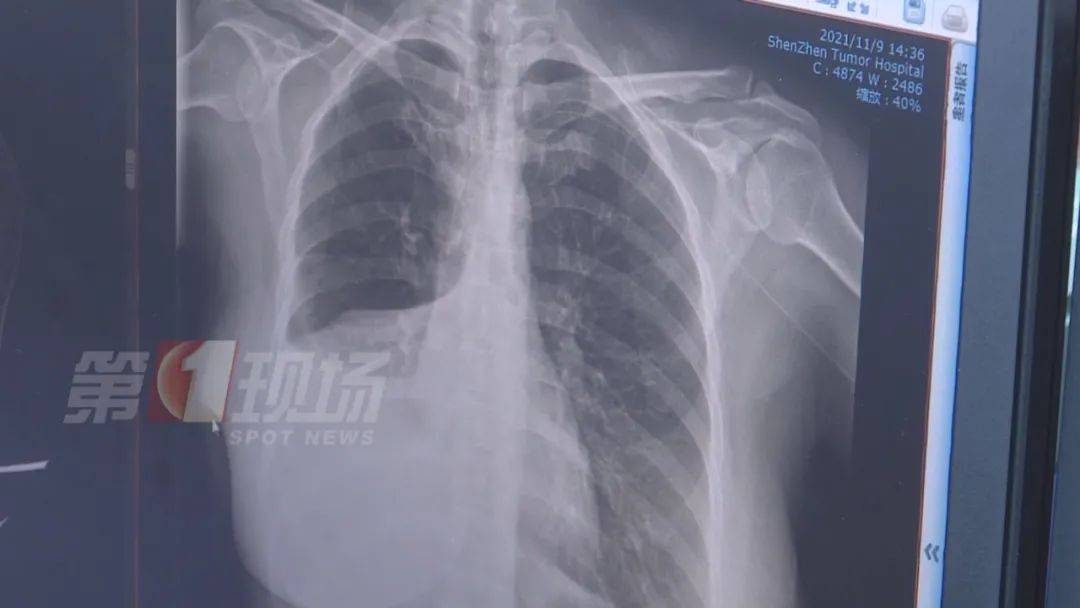

江女士做了增强CT后 , 确实发现肺部有一个五公分左右的肿瘤 , 医生诊断为肺癌 , 目前为中期偏早 , 建议她进行切除手术 。